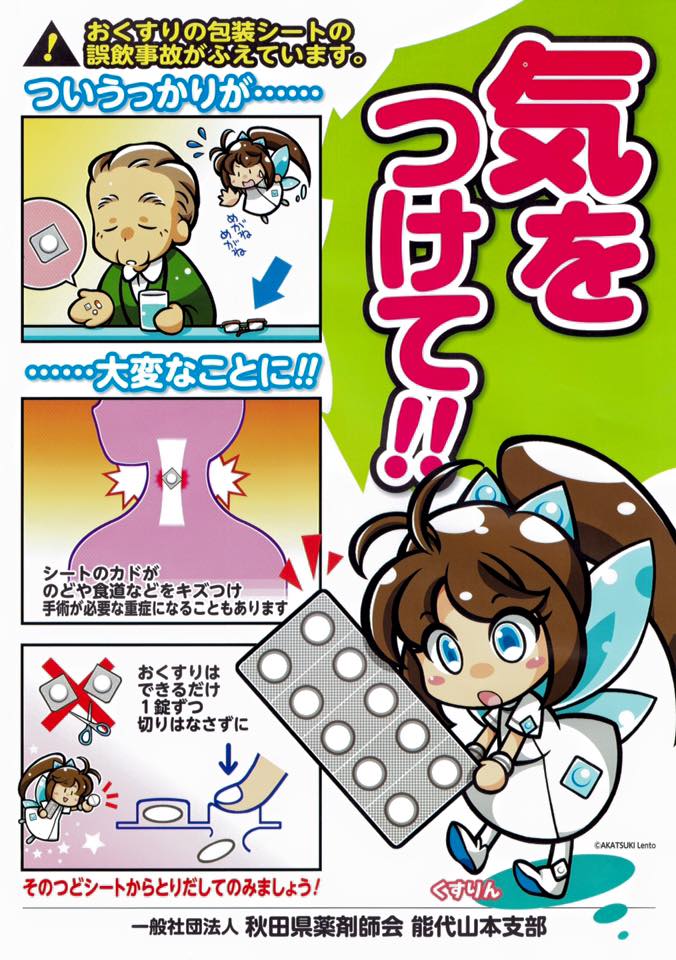

高齢者に多い事故 薬の包装シート Ptp 誤飲 はなぜ怖いのか

高齢者の誤飲 誤食が増加中 最も危ないのは薬の包装シート 不慮の

高齢者の誤飲食で最も多い 薬の包装の誤飲 に注意しましょう Rme

のどや食道を傷つけることも 薬の包装シートの誤飲に注意 萩市

包装シートの誤飲 はな薬局 宮崎市にある調剤薬局のはな薬局です